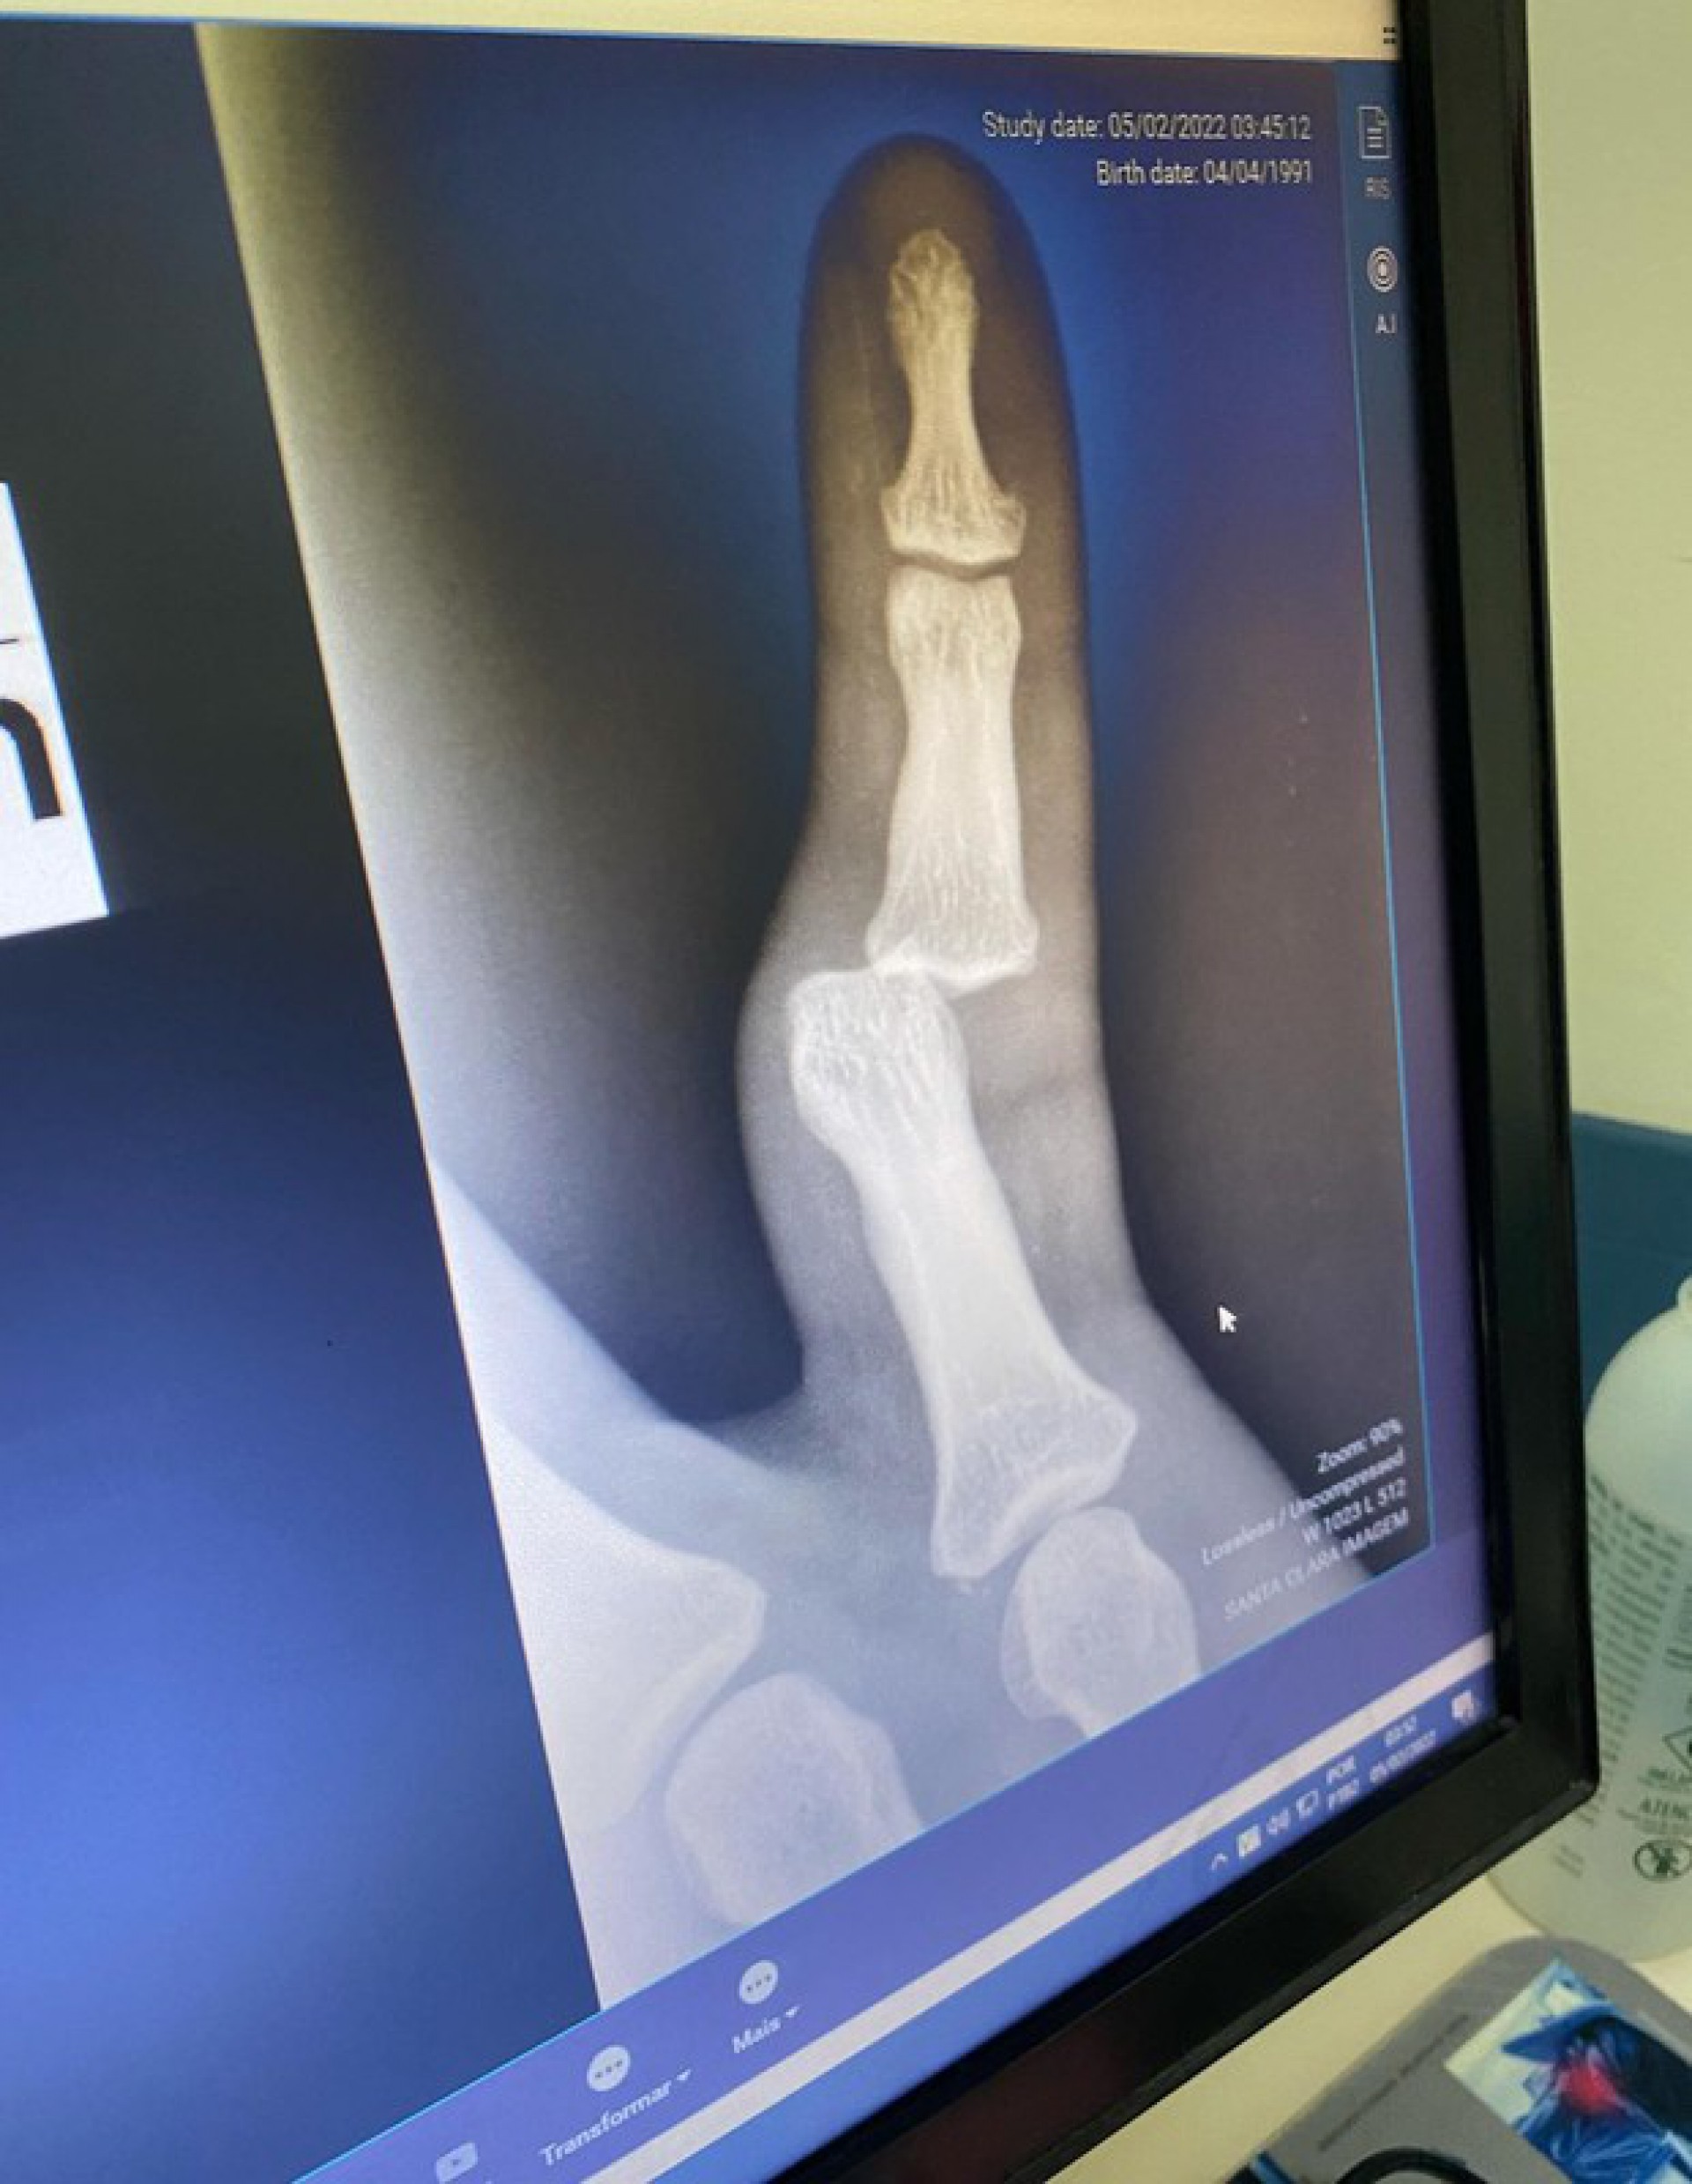

Nos stories, Lucas Lucco explicou o ocorrido. "Bebi demais ontem, levei um tombo ali perto da escada e caí em cima do dedo", contou.